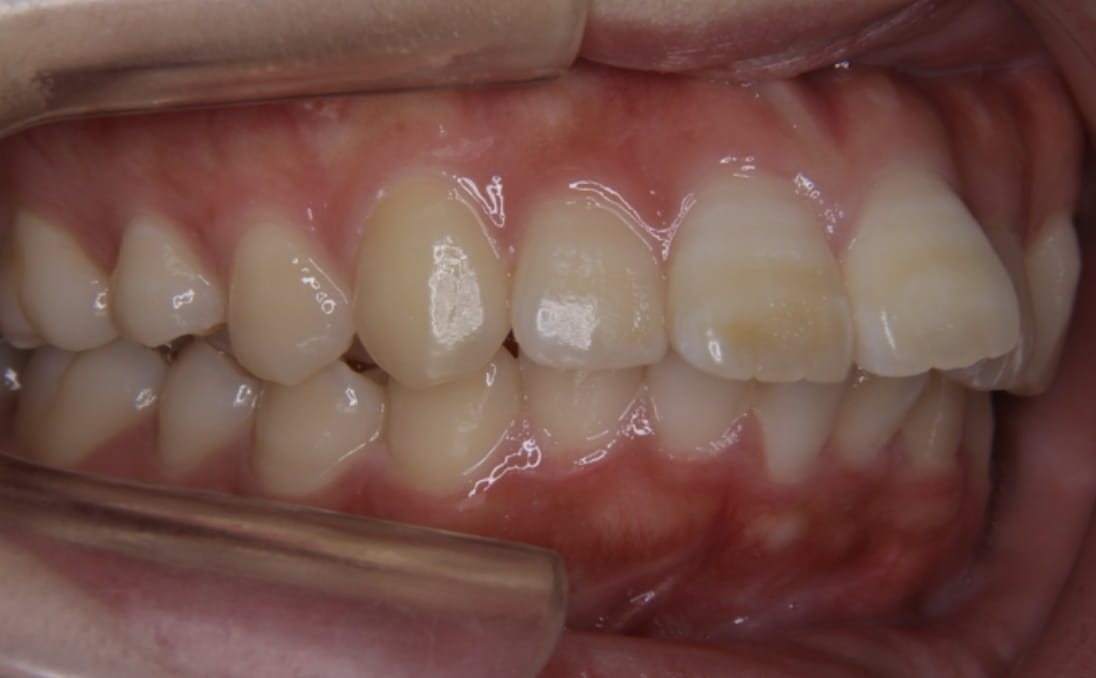

《歯槽性上下顎前突を伴う叢生》

症例42

性別:女性 年齢:13歳 お住まいの地域:奈良市

主訴 上の2本が出てるのが気になる

治療装置 上裏側、下表側からのハーフリンガル矯正装置

抜歯 上下4本

治療期間 2年8ヶ月

診断名 歯槽性上下顎前突を伴う叢生

副作用 歯肉退縮・歯根吸収・歯髄壊死・癒着による予期せぬ歯の動き

より綺麗にする希望を達成するために上下4本を抜歯。前歯のリトラクション(後方移動)を行うためにインプラントを使用。若年層ではあるが、インプラントの安定がよく、ヘッドギアに切り替えることなく、順調に進められた。

治療前